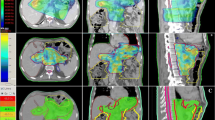

Figure 1 shows a qualitative comparison of TOMO plans and VE-HD and SYN plans for the different pathologies.